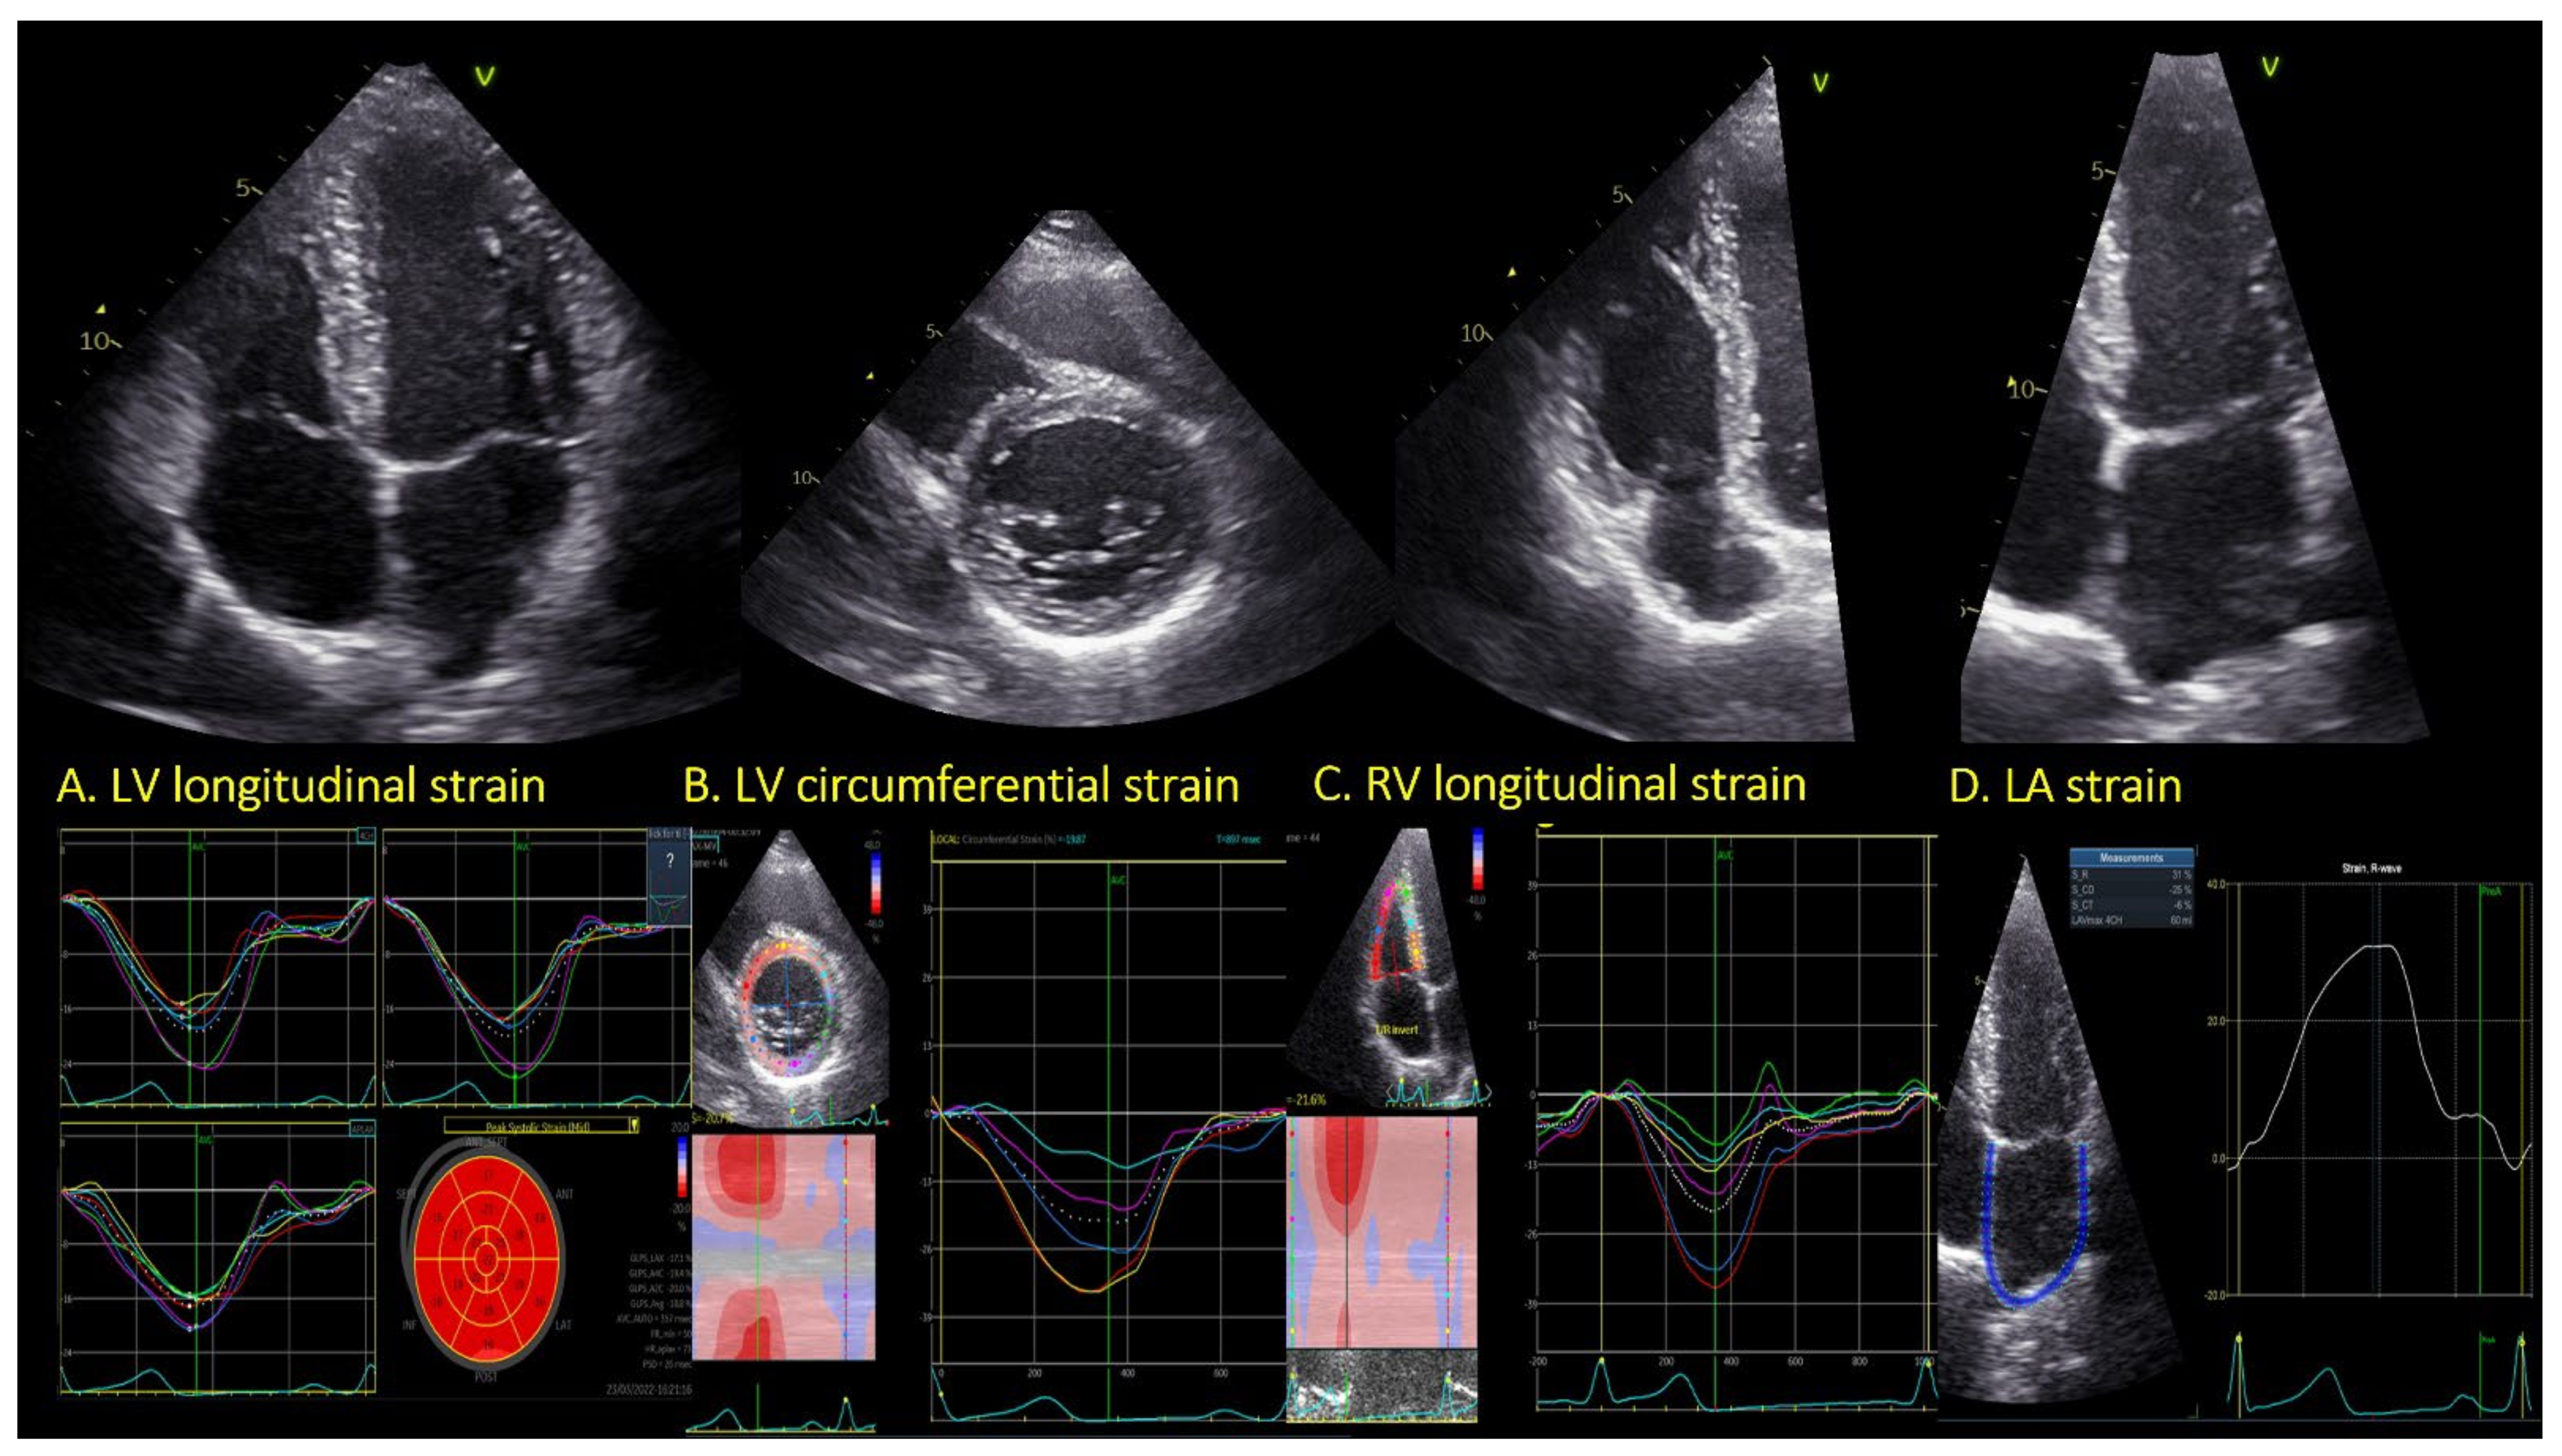

2.3.1. Left Ventricular Strain

2.3.2. Right Ventricular Strain

2.3.3. Left Atrial Strain

3.3.1. LV Strain Analysis

3.3.2. RV Strain Analysis

3.3.3. LA Strain Analysis

| Left ventricle | ||||

| GLS endocardial | % | −22.7 ± 2.5 | −22.6 ± 3.0 | 0.82 |

| GLS myocardial | % | −19.7 ± 2.2 | −19.7 ± 2.5 | 0.88 |

| GLS epicardial | % | −17.2 ± 2.0 | −17.3 ± 2.4 | 0.74 |

| PSD | ms | 32.2 ± 9.8 | 28.9 ± 11.4 | 0.06 |

| GCS | % | −20.4 ± 3.0 | −22.3 ± 3.1 | 0.001 |

| Right ventricle | ||||

| RV GLS | % | −21.8 ± 3.4 | −23.1 ± 3.3 | 0.04 |

| RV free wall | % | −25.9 ± 4.1 | −27.7 ± 3.8 | 0.02 |

| Left atrium | ||||

| LAS res | % | 34.2 ± 7.3 | 38.0 ± 6.9 | 0.001 |

| LAS ct | % | 11.2 ± 5.2 | 11.2 ± 5.2 | 0.83 |